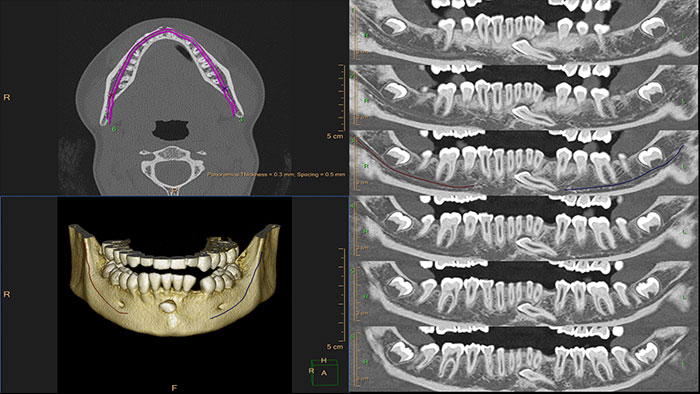

Planowanie zabiegu w chirurgii szczękowej

W urazach twarzoczaszki o przebiegu leczenia często można zadecydować wyłącznie po konsultacji chirurgicznej. Aplikację CT Dental Planning opracowano z myślą o usprawnieniu planowania zabiegów chirurgicznych oraz ułatwieniu współpracy między radiologami i chirurgami.